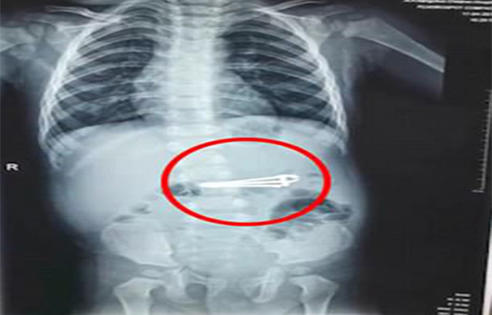

چینی بچے نے ناخن تراش اتفاقاً نگل لیا

چانگچونگ .....  چین کے اِس  شمال مشرقی علاقے میں ایک 16ماہ کے بچے نے اتفاقاً اپنی ماں کا نیل کٹر (ناخن تراش) نگل لیا جس کی ماں کو خبر نہ ہوسکی تاہم ناخن تراش پیٹ میں جاتے ہی اسے تکلیف شروع ہوگئی تو اسے اسپتال لیجایا گیا جہاں ایکسرے سے پتہ چلا کہ اسکے پیٹ میں نیل کٹر پڑا ہوا ہے۔اسکے والدین کا کہناہے کہ بچے کی حالت اچانک بگڑنے پر انہیں شک ہوا تھا کہ نیل کٹر نگل لیا ہے  اس لئے انہوں نے اس خیال  سے اسکی پیٹھ بھی تھپتھپائی کہ بچہ نیل کٹر اُگل دے مگر ایسا نہیں ہوا تو انہیں اسپتال کا رخ کرنا پڑا۔ خیر گزری کہ ناخن تراش پیٹ میں زیادہ نیچے تک نہیں گیا تھا اسی لئے ڈاکٹر  اسے ایک چمٹے سے بآسانی باہر کھینچ لینے میں کامیاب رہے۔ بچے کی ماں نے نیو کلچر پوسٹ نامی جریدے کو انٹرویو میں بتایا کہ ان کا بیٹا فیفی بستر پر بیٹھا ہوا تھا اور وہ ناخن کاٹ کر فارغ ہوئی تھیں۔ بس ذرا سی غفلت میں بچے نے نیل کٹر پر جھپٹا مارا ، منہ میں ڈالا او رنگل لیا۔ چمٹے سے نیل کٹر باہر نکالنے کیلئے 16مہینے کے بچے کو تھوڑی دیر کیلئے اینستھیسیا بھی دیا گیا تھا۔